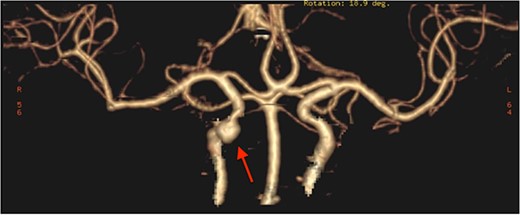

The patient underwent functional endoscopic sinus surgery. Her surgery was uneventful, and all sinuses were opened and cleaned from polyps and fungal debris. During surgery, a non-pulsating bulging at the lower lateral region of the right sphenoid sinus was noticed. This swelling was thought to be a bulging of a dehiscent ICA which may be a normal variant in some patients. Therefore, this bulging mass was not touched and was totally avoided during the procedure. The postoperative recovery period was uneventful and she was discharged the following day. However, on the 13th postoperative day, she presented to the emergency department with severe epistaxis, unconscious and blood pressure was unrecordable. After resuscitation with intravenous fluids and massive blood transfusion with 17 units of packed RBCs, the patient relatively improved and regained consciousness. Anterior and posterior nasal packs were inserted. The CT angiography showed pseudoaneurysm in the petrous segment of the right ICA (Fig. 2). The interventional radiologist performed occlusion with ballooning of right ICA for 45 min without developing motor or cognitive dysfunction, indicating a good compensation by the left ICA. Total occlusion, using multiple coils, was deployed proximal and distal to the aneurysm. Patient was discharged 2 days later. During the follow-up of more than 10 years no neurological deficit was noticed. Recent CT scan showed stable sinus disease and total occlusion of the right ICA (Fig. 3).

CT angiography, showing pseudoaneurysmal dilatation at the petrous segment of the right ICA.